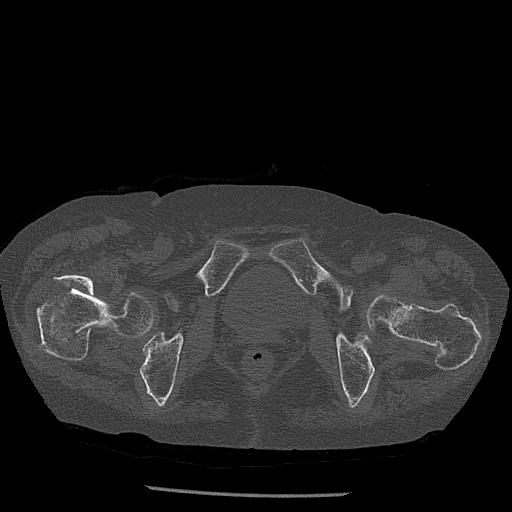

100703 1/27 両股正面+軸 1/29 両股正面+軸 94歳女性 パンソンロン